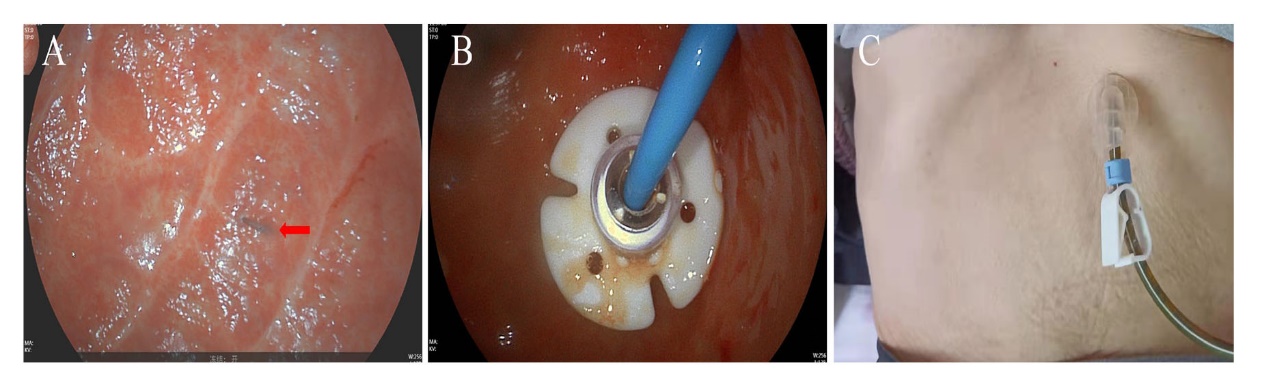

患者入院后于2021年8月24日行胃镜检查提示食管入口、食管中下段距门齿约30~40 cm处明显狭窄(图1A),予探条扩张后方能入镜至胃内,见胃窦变形,小弯侧大片溃疡形成,底覆白苔,周边黏膜充血水肿,幽门结构难以辨认(图1B),予球囊扩张(图1C),并放置鼻空肠管,术后第二天予肠内营养,但患者出现恶心、呕吐以及腹胀症状。2021年8月25日行上消化道碘剂造影显示食管上段、中下段狭窄,造影剂通过欠顺畅(图2);部分胃体、胃窦僵硬、狭窄并梗阻。心理科会诊提示患者有消极轻生念头,考虑为抑郁焦虑状态。经上述治疗后,患者肠内营养耐受情况欠佳,病情未见明显改善,梗阻仍然存在。经医务人员综合评估,确认该患者具有行PEG/J的适应证,无禁忌证。获得患方知情同意后,于2021年8月28日在气管插管全身麻醉下行PEG/J。患者取仰卧位,麻醉后经口插入胃镜,见食管仍狭窄,入镜至胃内,见胃腔变形,胃底较多胃液潴留,吸净后继续入镜至胃窦、幽门前区,见幽门仍狭窄,仔细辨认后送镜至十二指肠,见球部、降段黏膜光滑,退镜至胃体部,注气后于左上腹反复运用传统指压试验及透光试验寻找理想穿刺点,由于胃腔变形、胃移位,术者反复多次选点失败,后联合运用负压针吸试验,用含5 mL 生理盐水的注射器抽吸针筒保持负压,同时保证胃腔内充分注气,再次选定穿刺点后经腹部皮肤逐层缓慢穿刺至胃腔(图3A),最终定位于剑突下2 cm偏左约3 cm,消毒铺巾后,采用牵拉法完成胃造瘘术,并经胃造瘘管(管径6 mm)送入小肠管(管径3 mm)至空肠上段(图3B[5]。患者术中、术后生命体征平稳。于术后6 h开始向小肠管内注入少量营养液并逐量增加至正常管饲量,后逐渐过渡至日常食糜。经处理,患者病情及营养状况逐渐好转,于2021年9月25日出院。1个月后患者遵嘱返院复诊,监测体质量由住院期间最轻时39 kg增至47 kg,复查碘剂造影示食管上段狭窄较前减轻,中下段食管狭窄;胃窦部至幽门区明显狭窄伴梗阻,仅见少许造影剂通过幽门。医师与患方保持电话随访至撰稿日,得知患者呕吐次数逐渐减少至缓解,营养状况持续改善,造瘘管固定良好,造瘘口无红肿、渗液等(图3C)。

图3 一例上消化道严重腐蚀伤患者的PEG/J及腹部图片

注:A为负压针吸试验时注射器针头(箭头所示)刺入胃腔;B为经胃造瘘管送入小肠管至空肠上段;C为术后随访造瘘管、造瘘口情况良好。